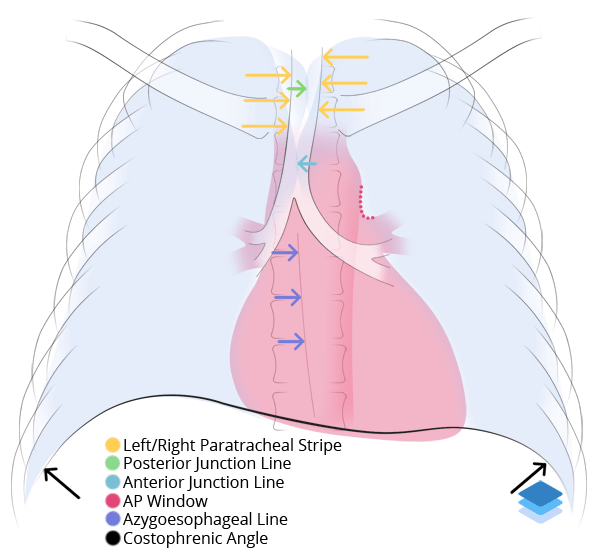

Chest

Chest

Chest radiograph & CT anatomy

Chest

Chest

Chest radiograph & CT anatomy